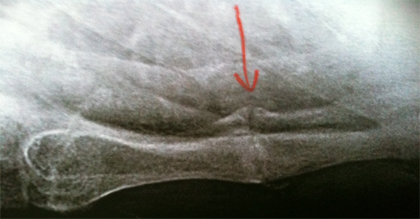

Cas clinique N°51

Dr Véra Lemaire Paris

Il s'agit d'un jeune homme âgé de 26 ans qui a déjà consulté plusieurs fois pour une douleur thoracique antérieure diurne et nocturne.

Il n'a pas d'antécédents particuliers et l'examen clinique est normal, en dehors d'une douleur réveillée par la pression du manubrium sternal.

La CRP est normale.

On lui a parlé de fracture alors qu'il n'y a pas eu de traumatisme.

Un AINS est partiellement efficace.

Quels examens demandez-vous ?

Quel(s) diagnostic, quel(s) traitement(s) proposez-vous ?